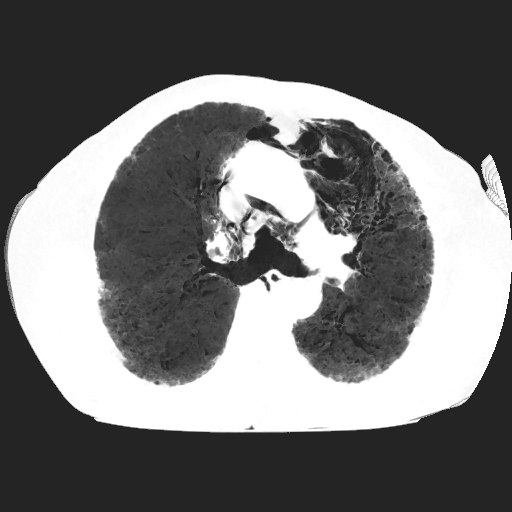

El parénquima pulmonar izquierdo muestra un infiltrado intersticial difuso que causa engrosamiento del septum axial, además del fenómeno de bronquiectasias quísticas se observan pequeñas bulas enfisematosas de localización subpleural que compromete ambas bases pulmonares.

Se observan imágenes de vidrio despulido en todo el lóbulo inferior izquierdo, el cual compromete los segmentos de la língula del segmento superior y medio

El parénquima pulmonar derecho muestra infiltrado intersticial en imagen de vidrio despulido con evidencia de lesiones subpleurales que representan bullas enfisematosas de diferentes tamaños.

Al utilizar un contraste Minip, se observan bronquiectasias cilíndricas en el extremo del lóbulo superior derecho, observándose un patrón de panal de abeja situada en la región apical del lóbulo superior izquierdo.

Bronquiectasias cilíndricas, bullas enfisematosas basales bilaterales